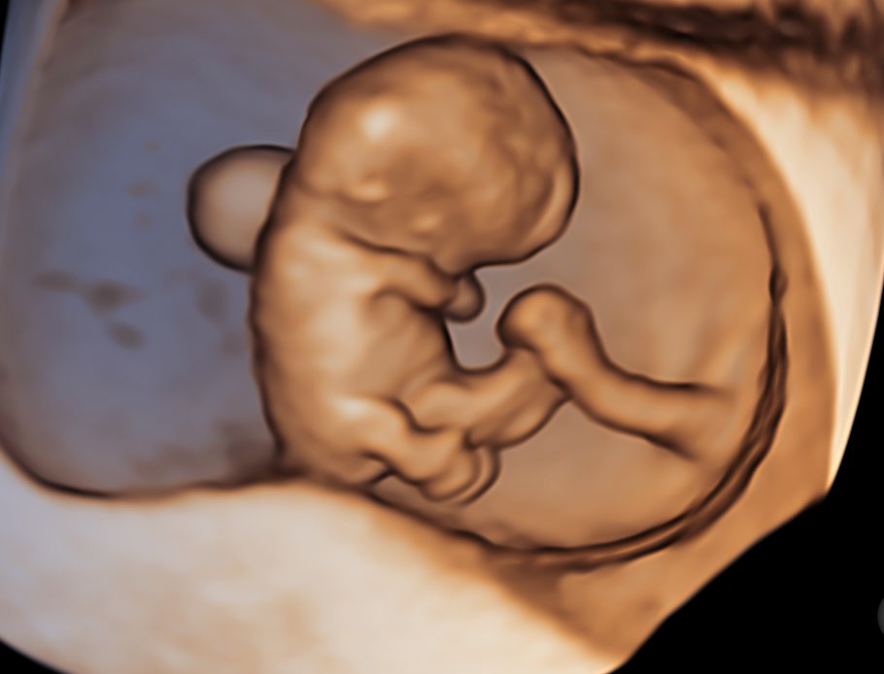

• HDliveTM technologies

• Automation technologies with SonoBiometry, SonoNTTM, SonoIT

El Voluson Signature 18 se basa en un nuevo motor de imágenes: la arquitectura Voluson Unity, que ofrece velocidades de procesamiento y velocidades de fotogramas más rápidas que nuestros sistemas Signature anteriores. Este hardware y software son la base del sistema y sientan las bases para las capacidades actuales y futuras. Experimente ahora un nuevo nivel de profundidad y claridad.

Procesamiento rápido de volumen 3D/4D